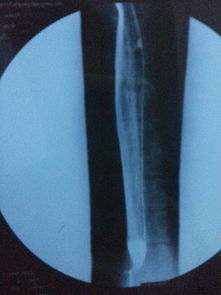

為了保證檢查準(zhǔn)確,做食道鋇餐檢查早晨不能吃飯喝水,包括肝功,血脂,血糖等檢查也是這樣要求的.X線(xiàn)鋇餐檢查 食管X線(xiàn)鋇餐檢查可顯示鋇劑在癌腫點(diǎn)停滯,病變段鋇流細(xì)窄;食管壁僵硬,蠕動(dòng)減弱,粘膜紋變粗而紊亂,邊緣毛糙;食管腔狹窄而不規(guī)則,梗阻上段輕度擴(kuò)張,并可有潰瘍壁龕及棄盈缺損等改變。

常規(guī)X線(xiàn)鋇餐檢查常不易發(fā)現(xiàn)淺表和小癌腫。應(yīng)用甲基纖維素鈉(sodium methyl cellulose)和鋇劑作雙重對(duì)比造影,可更清楚地顯示食管粘膜,提高食管癌的發(fā)現(xiàn)率。